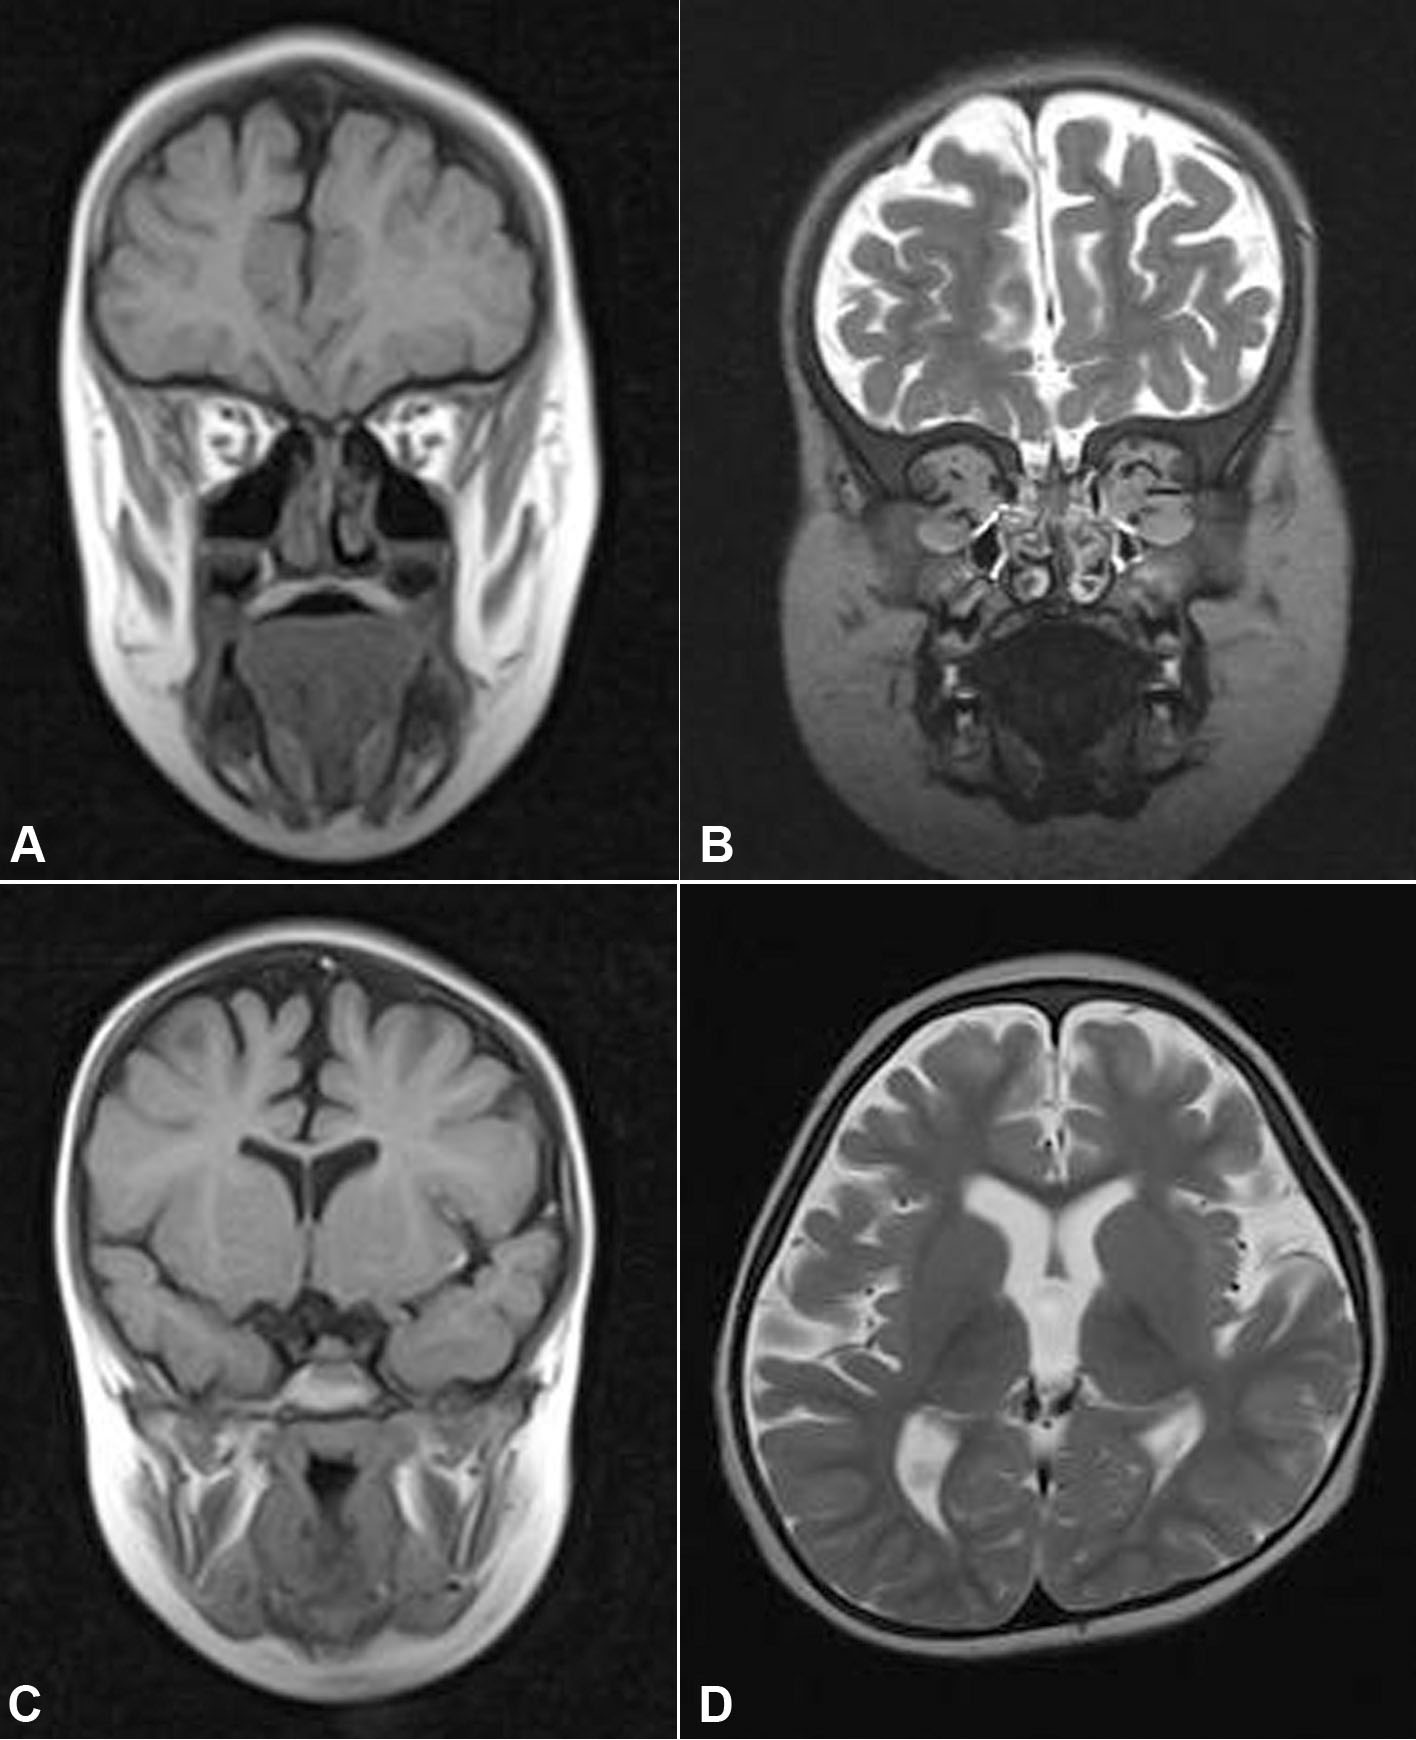

Figure 3. Cerebral and orbital MRI

images. A: Family A, Patient IV:5. B: Family B,

affected daughter. Orbital hypoplasia. Coronal images,

T2-weighted. Agenesis of the eye globes. Rudimentary extraocular

muscles. Present and normal lacrimal glands. C: Axial

image. T1-weighted. Family A, patient IV:5. Absent frontal

sinus. D: Axial image. T2-weighted. Family B, affected

daughter. Corticosubcortical atrophy, predominantly in the

frontotemporal lobes, with ex vacuo dilation of the ventricles.